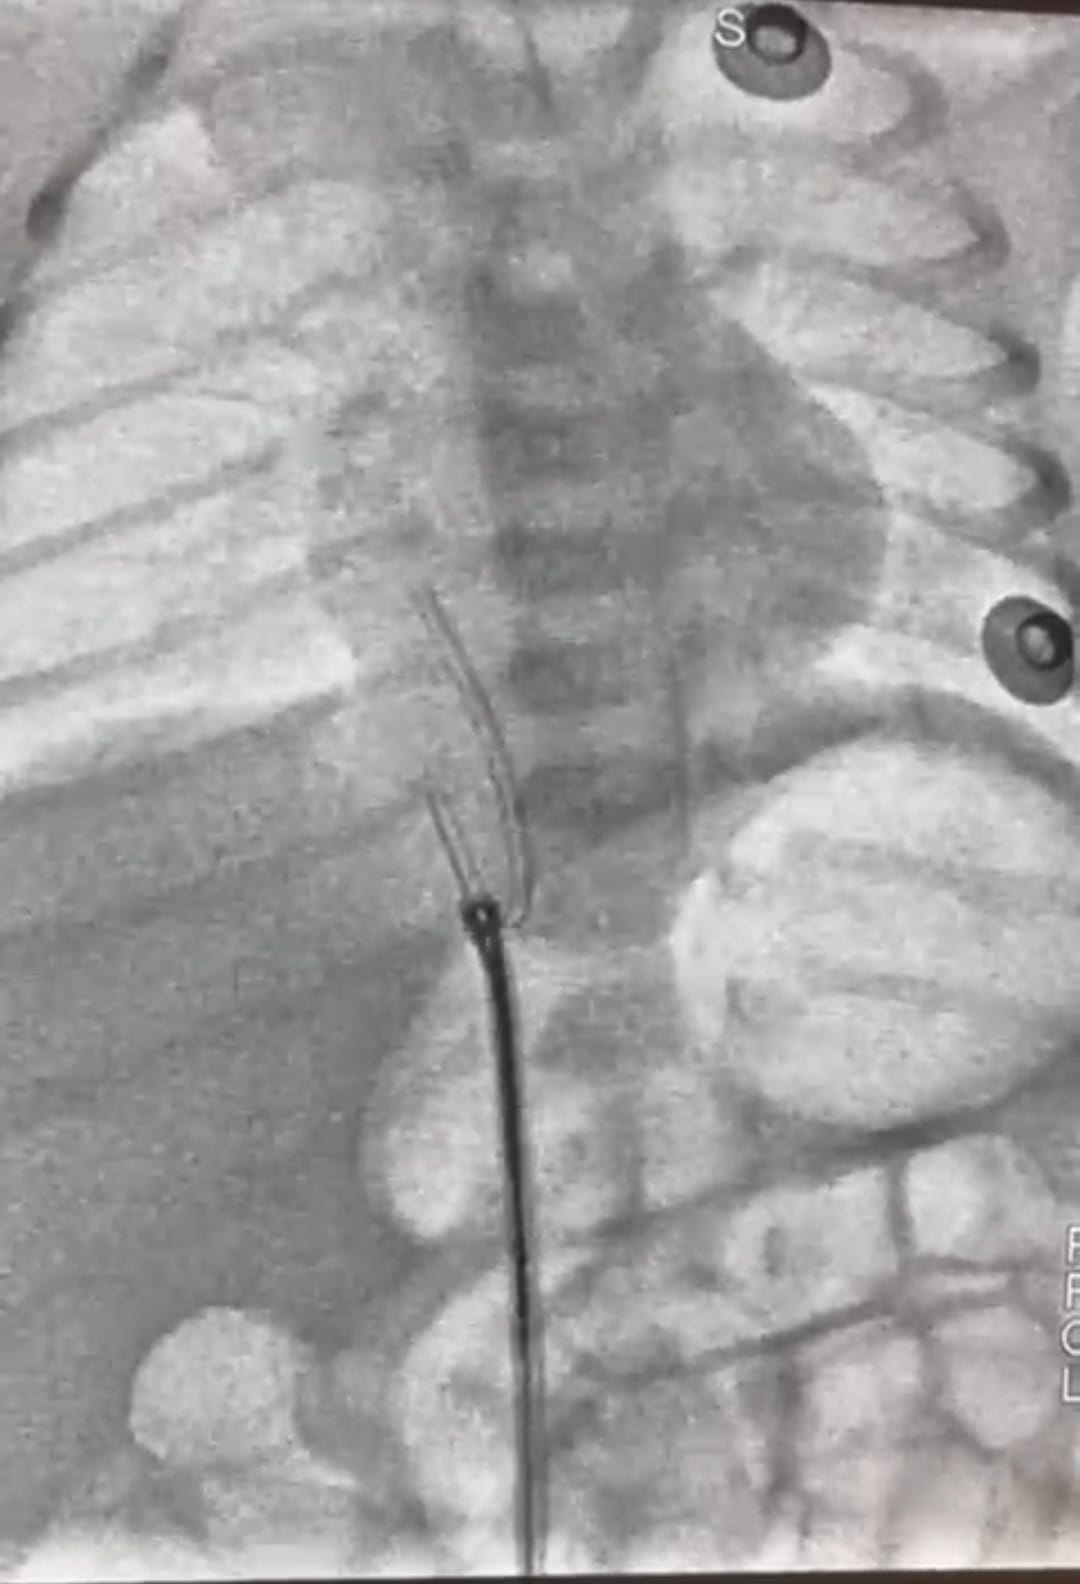

وأفاد الدكتور محمد عبد الهادى عميد معهد القلب القومى بأن طفل حديث الولادة، يبلغ من العمر 5 أيام فقط، قد وصل إلى المعهد في حالة حرجة، بعد أن تحرك جزء من قسطرة السرة من مكانه واستقر في قلب الطفل، وهذه القسطرة تستخدم أحياناً لإدخال السوائل والأدوية، وقد استدعت هذه الحالة تدخلاً سريعًا ودقيقًا، وعلى الفور قام فريق عمل الحضانة،، فى التنسيق لدخول الحالة أول أيام العيد وتجهيزها للتدخل الجراحى، وقام فريق طبي متميز بإجراء القسطرة العاجلة للرضيع. وبفضل الله ومهارة الفريق الطبي، تم استخراج قسطرة السرة بنجاح ودون مضاعفات، والرضيع الآن في حالة مستقرة، وقد غادر الحضانة إلى منزله في حالة جيدة وبدون أي مضاعفات.

وأضاف عميد المعهد أنه ساهم في هذا الإنجاز الطبي فريق متكامل من الأطباء والتمريض والفنيين من أبناء المعهد تحت قيادة أ. د. أحمد معوض الإمام إستشارى القلب وقسطرة العيوب الخلقية بالمعهد، وأ. د. رشا حسني.. رئيس قسم التخدير، وأ. د. أحمد جمال ندا.. زميل التخدير، د. هبة وشاحى .. استشارى الحضانات والرعاية، ود. أحمد أبو هاشم ود. محمود صديق، ود. نعمة إبراهيم، ود. جهاد محمود.